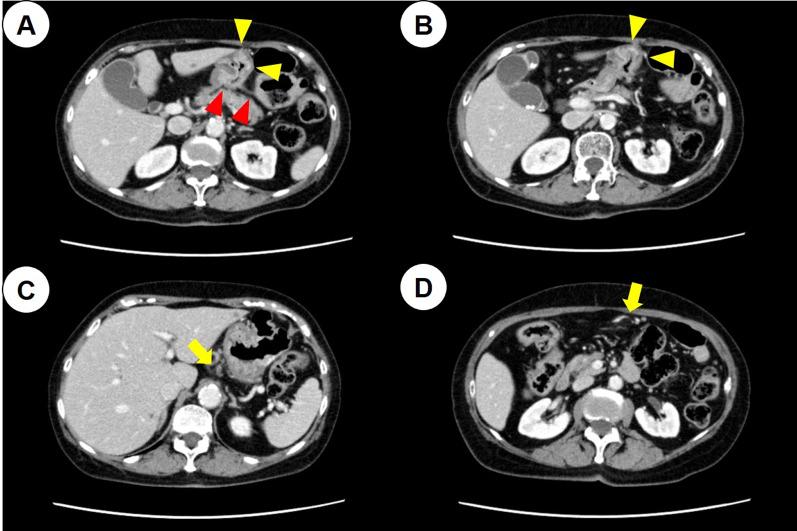

A 73-year-old woman presented with a type 3 tumor in the lower part of the gastric body, which was diagnosed as gastric cancer through biopsy. Staging laparoscopy revealed that the tumor had invaded the pancreas and the posterior lobe of the transverse mesocolon, and disseminated nodules were found near the ligament of Treitz. After 4 courses of S-1 plus cisplatin therapy, laparoscopic gastrojejunal bypass was performed because of difficulty in oral intake. She received S-1 plus oxaliplatin therapy after a gastrojejunal bypass; however, her regional lymph nodes were enlarged. After six courses of paclitaxel plus ramucirumab as second-line chemotherapy, computed tomography (CT) showed exacerbation of peritoneal dissemination; thus, nivolumab was selected as the third-line therapy. The tumor was characterized by MSI-high. At 24 courses, CT and gastroscopy revealed a complete clinical response of the tumor; however, re-growth of the primary tumor was observed at 36 courses. The patient underwent distal gastrectomy with D1 + lymph node dissection, and received S-1 monotherapy as adjuvant therapy for 1 year. No recurrence was noted at 39 months after the surgery.

一名73岁女性,胃体下部有一个3型肿瘤,经活检诊断为胃癌。分期腹腔镜检查显示肿瘤侵犯了胰腺和横结肠系膜后叶,在Treitz韧带附近发现了播散性结节。在接受4个疗程的S-1加顺铂治疗后,由于口服摄入困难,进行了腹腔镜胃空肠吻合术。胃空肠吻合术后,她接受了S-1加奥沙利铂治疗;然而,她的区域淋巴结肿大。在接受六个疗程的紫杉醇加雷莫西尤单抗作为二线化疗后,计算机断层扫描(CT)显示腹膜播散加重;因此,选择纳武单抗作为三线治疗。肿瘤的特征为MSI-H。在第24个疗程时,CT和胃镜检查显示肿瘤有完全的临床反应;然而,在第36个疗程时观察到原发肿瘤复发。患者接受了D1+淋巴结清扫的远端胃切除术,并接受S-1单药辅助治疗1年。术后39个月未发现复发。